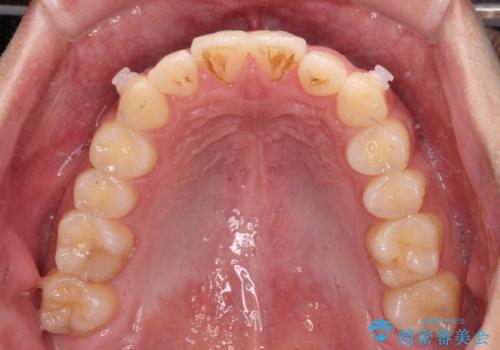

捻れて飛び出した前歯 インビザラインで整った前歯に

歯と歯の間を削ることでうまくスペースコントロールでき、また、毎日22時間以上しっかりとマウスピースを装着していただいたので、スムーズに治療が進みました。

治療途中で転勤となり、遠方からの通院となったため、来院間隔空いてしまいましたが、2年間で終えることができました。